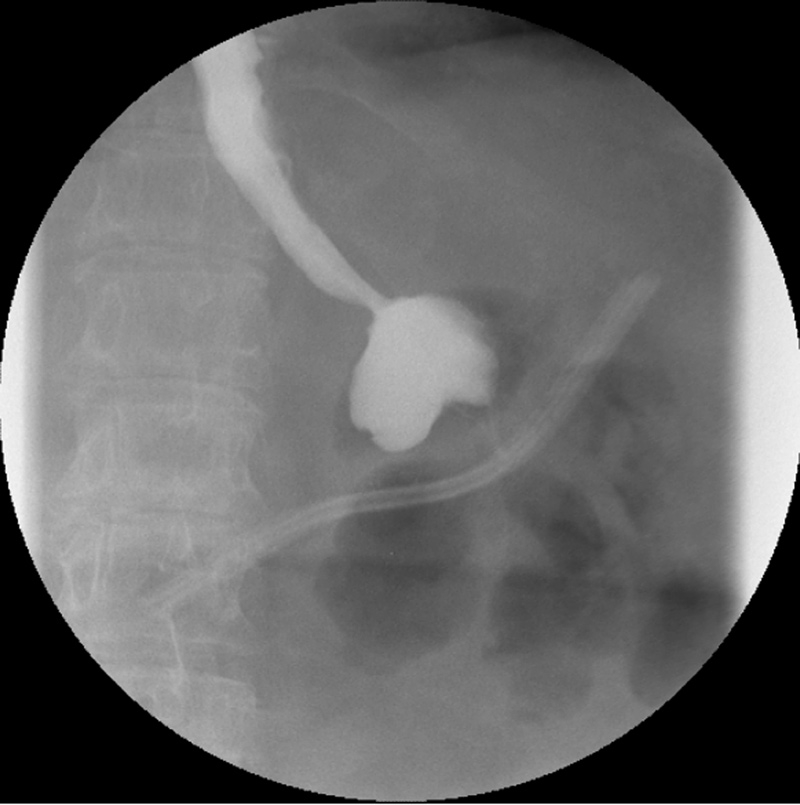

Figure 1

Upper Gastrointestinal series showing a stomal obstruction at the level of the gastrojejunal anastomosis.

In two patients, the results showed a stoma obstruction due to a postoperative edema at the level of the GJ anastomosis (1.2%) (fig. 1). The post gastric bypass diet was delayed and the UGI was performed again at postoperative day 4 with resolution of the edema. One patient presented an anastomotic stenosis at the level of the JJ anastomosis with delayed emptying (0.6%) (fig. 2). The patient was treated conservatively with success as well. Of note, the patients who presented an abnormal UGI study were all symptomatic with early nausea and vomiting.